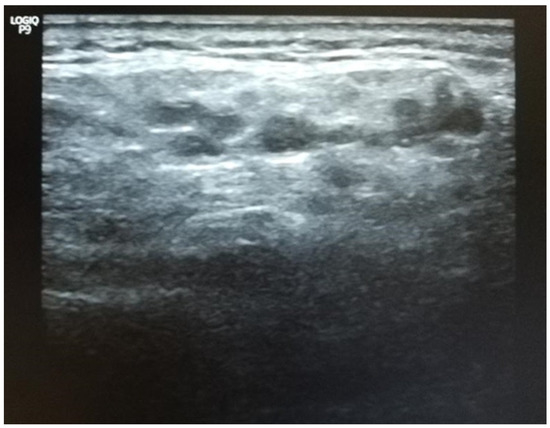

Although the patient was completely asymptomatic, the Schirmer test diagnosed severe eye dryness (4 mm for the left eye and 5 mm for the right eye). In addition, the parotid glands had some echographic particularities (see Figure 7).

Figure 7.

Ultrasound of the patient’s salivary glands. Grade 3, severe changes: diffuse inhomogeneity with anechoic/hypoechoic areas occupying the entire gland surface and surrounded by abnormal tissue and hyperechoic bands, corresponding to the scoring system described by S. Jousse-Joulin et al. [108]. Courtesy of Ciprian Jurcut, Internal Medicine Department, “Dr Carol Davila” Central Emergency University Military Hospital Bucharest, Romania.